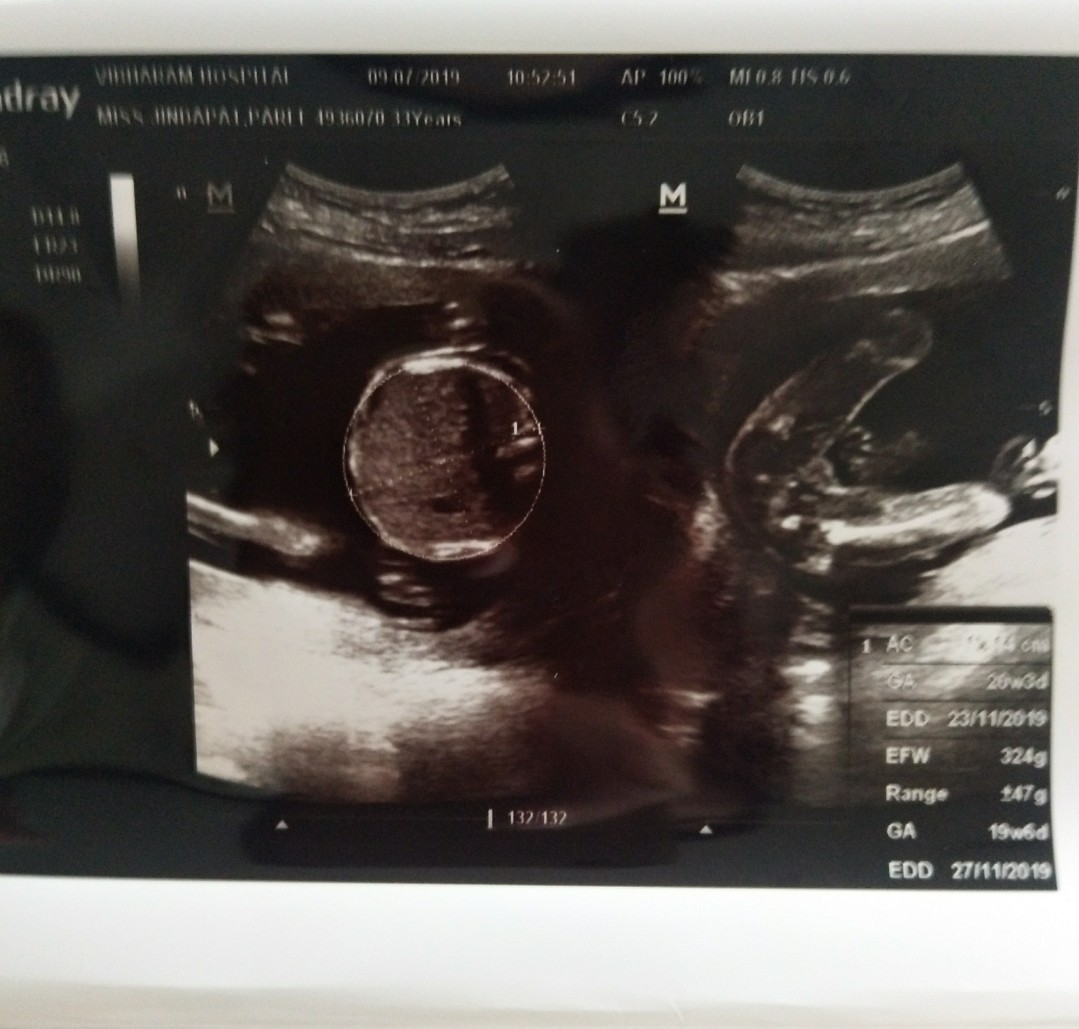

ไข่มาเป็นพวง😁😁😁

บ้านนี้ได้ลูกสาวคะ